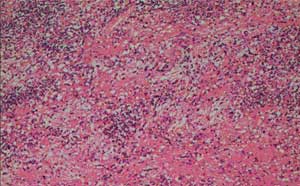

腹膜后恶性肿瘤治疗